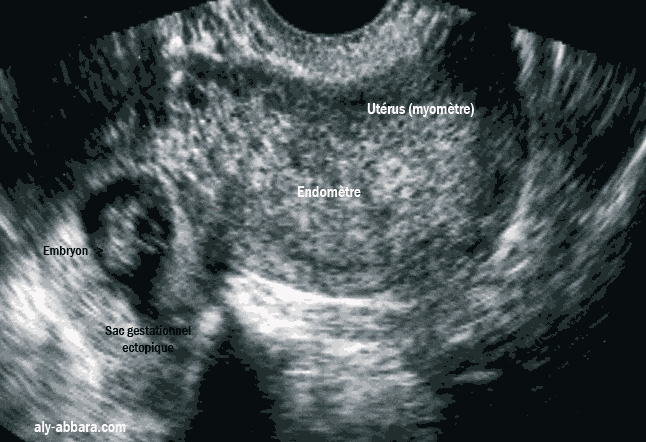

Grossesse ectopique tubaire droite avec un embryon de 12 mm de LCC, avec activité cardiaque présente

Image échographique montrant une grossesse extra-utérine avec la présence d’un sac gestationnel contenant un embryon de 12 mm de longueur crânio-caudale (7 semaines d'aménorrhée et 3 Jour) avec une activité cardiaque bien présente, taux de hCG plasmatique est de 62 000 UI/L.

À la cœlioscopie, il s'agit d'une grossesse extra-utérine tubaire non rompue et développée dans la portion moyenne et distale de trompe droite.